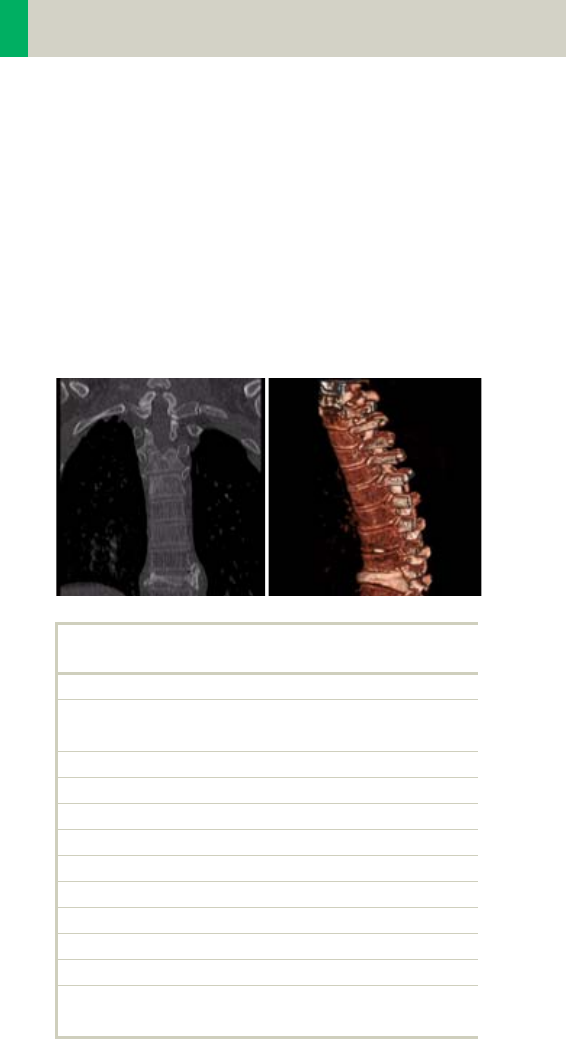

Thorax 226

•Overview 226

- General Hints 229

- Body Kernels 231

•Scan Protocols 232

- ThoraxRoutine/

ThoraxRoutine06s 232

- ThoraxCombi/

ThoraxCombi06s 235

- ThoraxVol 240

-ThoraxFast/

10

Contents

ThoraxFast06s 244

- ThoraxHR 246

- ThoraxHRSeq 250

- ThoraxECGHRSeq 252

-LungLowDose/

LungLowDose06s 254

-LungCARE/

LungCARE06s 258